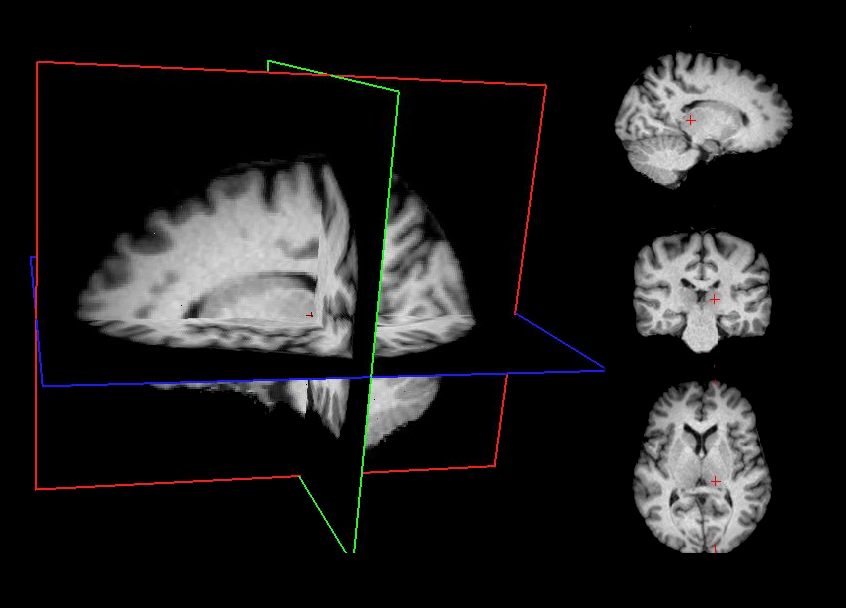

Minimally preprocessed data are generated using a standardized sequence of lightweight processing steps applied to the raw T1-weighted (T1w) MRI images. This workflow combines skull stripping, bias field correction, and spatial normalization using widely adopted neuroimaging tools. This minimal preprocessing pipeline ensures that the data are standardized and ready for subsequent processing stages while maintaining maximal fidelity to the original raw images.

• Skull stripping Brain extraction is performed using FreeSurfer’s deep learning–based mri_synthstrip method [1], which provides a robust and accurate removal of non-brain tissues.

• Bias field correction Intensity non-uniformities are corrected using the ANTs N4 algorithm [2], improving image homogeneity.

• Affine registration to MNI space Spatial alignment is carried out using FSL FLIRT [3] with a 9‑degree‑of‑freedom (DOF) affine transformation (translations, rotations, and scaling; no shearing). This step registers the T1w image to the MNI template while preserving overall anatomy.